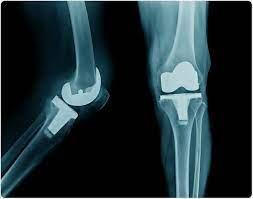

# 15 شهادة وقصص نجاح ملهمة بعد استبدال مفصل الركبة استبدال مفصل الركبة هو إجراء جراحي يهدف إلى تخفيف الألم وتحسين نوعي…

# 15 قصة وتجربة ملهمة لمرضى استبدال مفصل الركبة: استعادة الحياة والأمل إذا كنت تفكر في إجراء جراحة استبدال مفصل الركبة…

# قصص ملهمة: 15 تجربة ناجحة مع استبدال مفصل الركبة استبدال مفصل الركبة إجراء جراحي يهدف إلى تخفيف الألم وتحسين نوعية ا…